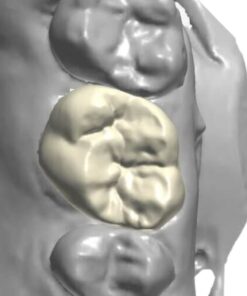

All on X Implant Bridge – CAD Design

Digitally designed All on X implant bridges by Viet Dental Lab. Restore full arches with CAD precision, esthetics, and long-term function on 4–6 implants.

All on X Implant Bridge - CAD Design